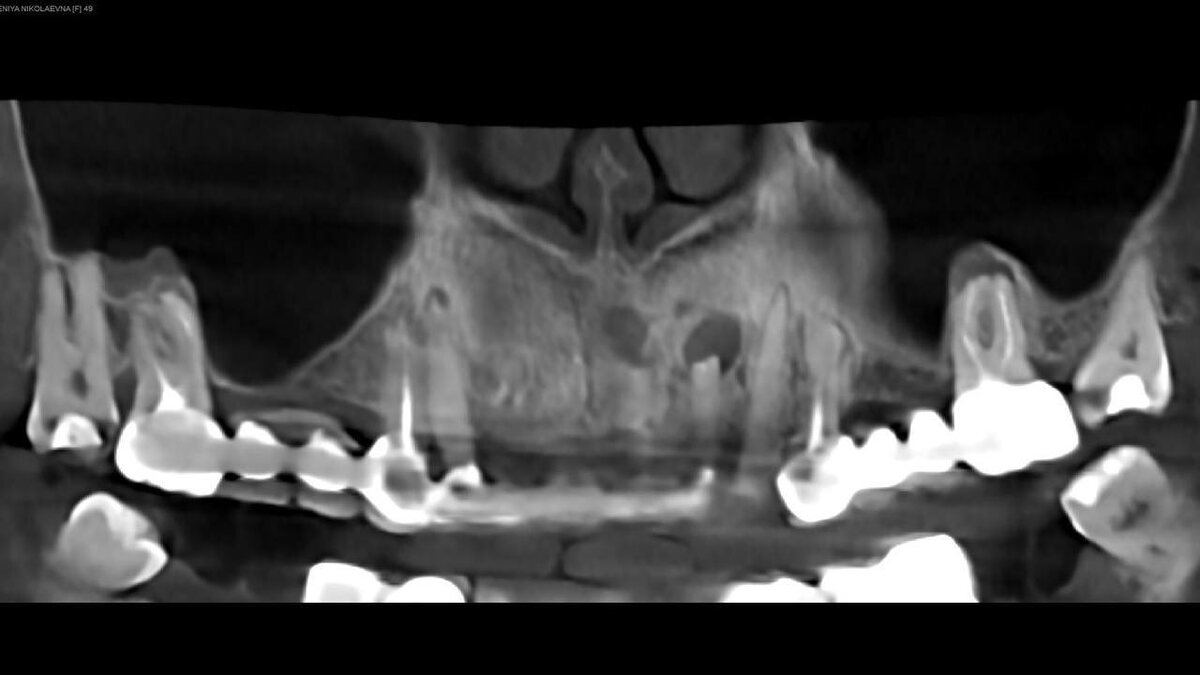

Дефицит кости по ширине. Качество костной ткани - D3-D4. Выраженная пневматизация верхнечелюстной пазухи.

Учитывая, что имплантаты А2 имеют самую толстую стенку при минимальном диаметре и допускают глубокое погружение принято решение обойтись без дополнительной костной пластики и установить имплантаты диаметром 3,5 мм в доступную кость.

Установлены имплантаты диаметром 3,5, длиной от 9,5 до 14 мм. Достигнута бикортикальная фиксация. После установки имплантатов зафиксированы мультиюниты (L).